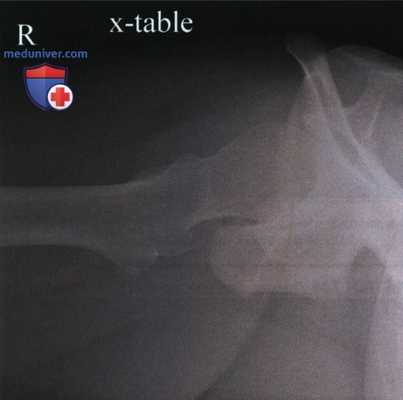

Рекомендации по анализу рентгенограммы тазобедренного сустава в аксиолатеральной проекции (нижневерхней, по методу Данелиуса-Миллера)

Рекомендации по анализу качества изображений (рис. 1):

РИСУНОК 1 Рентгенограмма тазобедренного сустава в аксиолатеральной проекции, правильное расположение.

• Мягкие ткани противоположного бедра не накладываются на головку бедренной кости или ее шейку

• Вертлужная впадина визуализируется в профиль.

• Верхняя ветвь таза видна медиальнее головки бедренной кости (рис. 4)

• Отсутствует проекционное укорочение шейки бедренной кости

• Большой и малый вертелы визуализируются приблизительно на одном уровне (рис. 5)

• Малый вертел виден в профиль сзади.

• Большой вертел накладывается на диафиз бедренной кости (рис. 6)

• Перелом проксимального отдела бедренной кости или ее шейки: рис. 7

• Вывих тазобедренного сустава: рис. 8

• Шейка бедренной кости находится в центре экспозиционного поля

• Вертлужная впадина, большой и малый вертелы, головка и шейка бедренной кости, седалищный бугор входят в экспозиционное поле

РИСУНОК 2 Правильное положение пациента для рентгенографии тазобедренного сустава в аксиолатеральной проекции. РИСУНОК 3 Правильные наклон таза, угол между бедренной костью и ЦП и положение ПИ для рентгенографии правого тазобедренного сустава в аксиолатеральной проекции (угол между ЦЛ и бедренной костью составляет 45°). РИСУНОК 4 Рентгенограмма тазобедренного сустава в аксиолатеральной проекции без наклона таза. Верхняя ветвь таза накладывается на головку бедренной кости и ее шейку. РИСУНОК 5 Рентгенограмма тазобедренного сустава в аксиолатеральной проекции. Угол между бедренной костью и ЦП был избыточным. РИСУНОК 6 Рентгенограмма тазобедренного сустава в аксиолатеральной проекции. Нижняя конечность была повернута наружу.